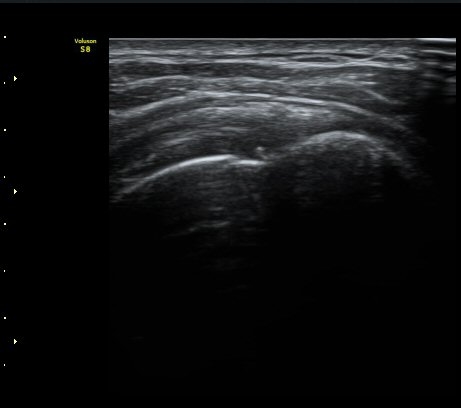

ÀÌµÎ¹Ú±Ù°Ç È¾´Ü¸é°Ë»ç¿¡¼­ ƯÀÌ ¼Ò°ßÀ» º¸ÀÌÁö ¾ÊÀ½(»çÁø 1, 2).